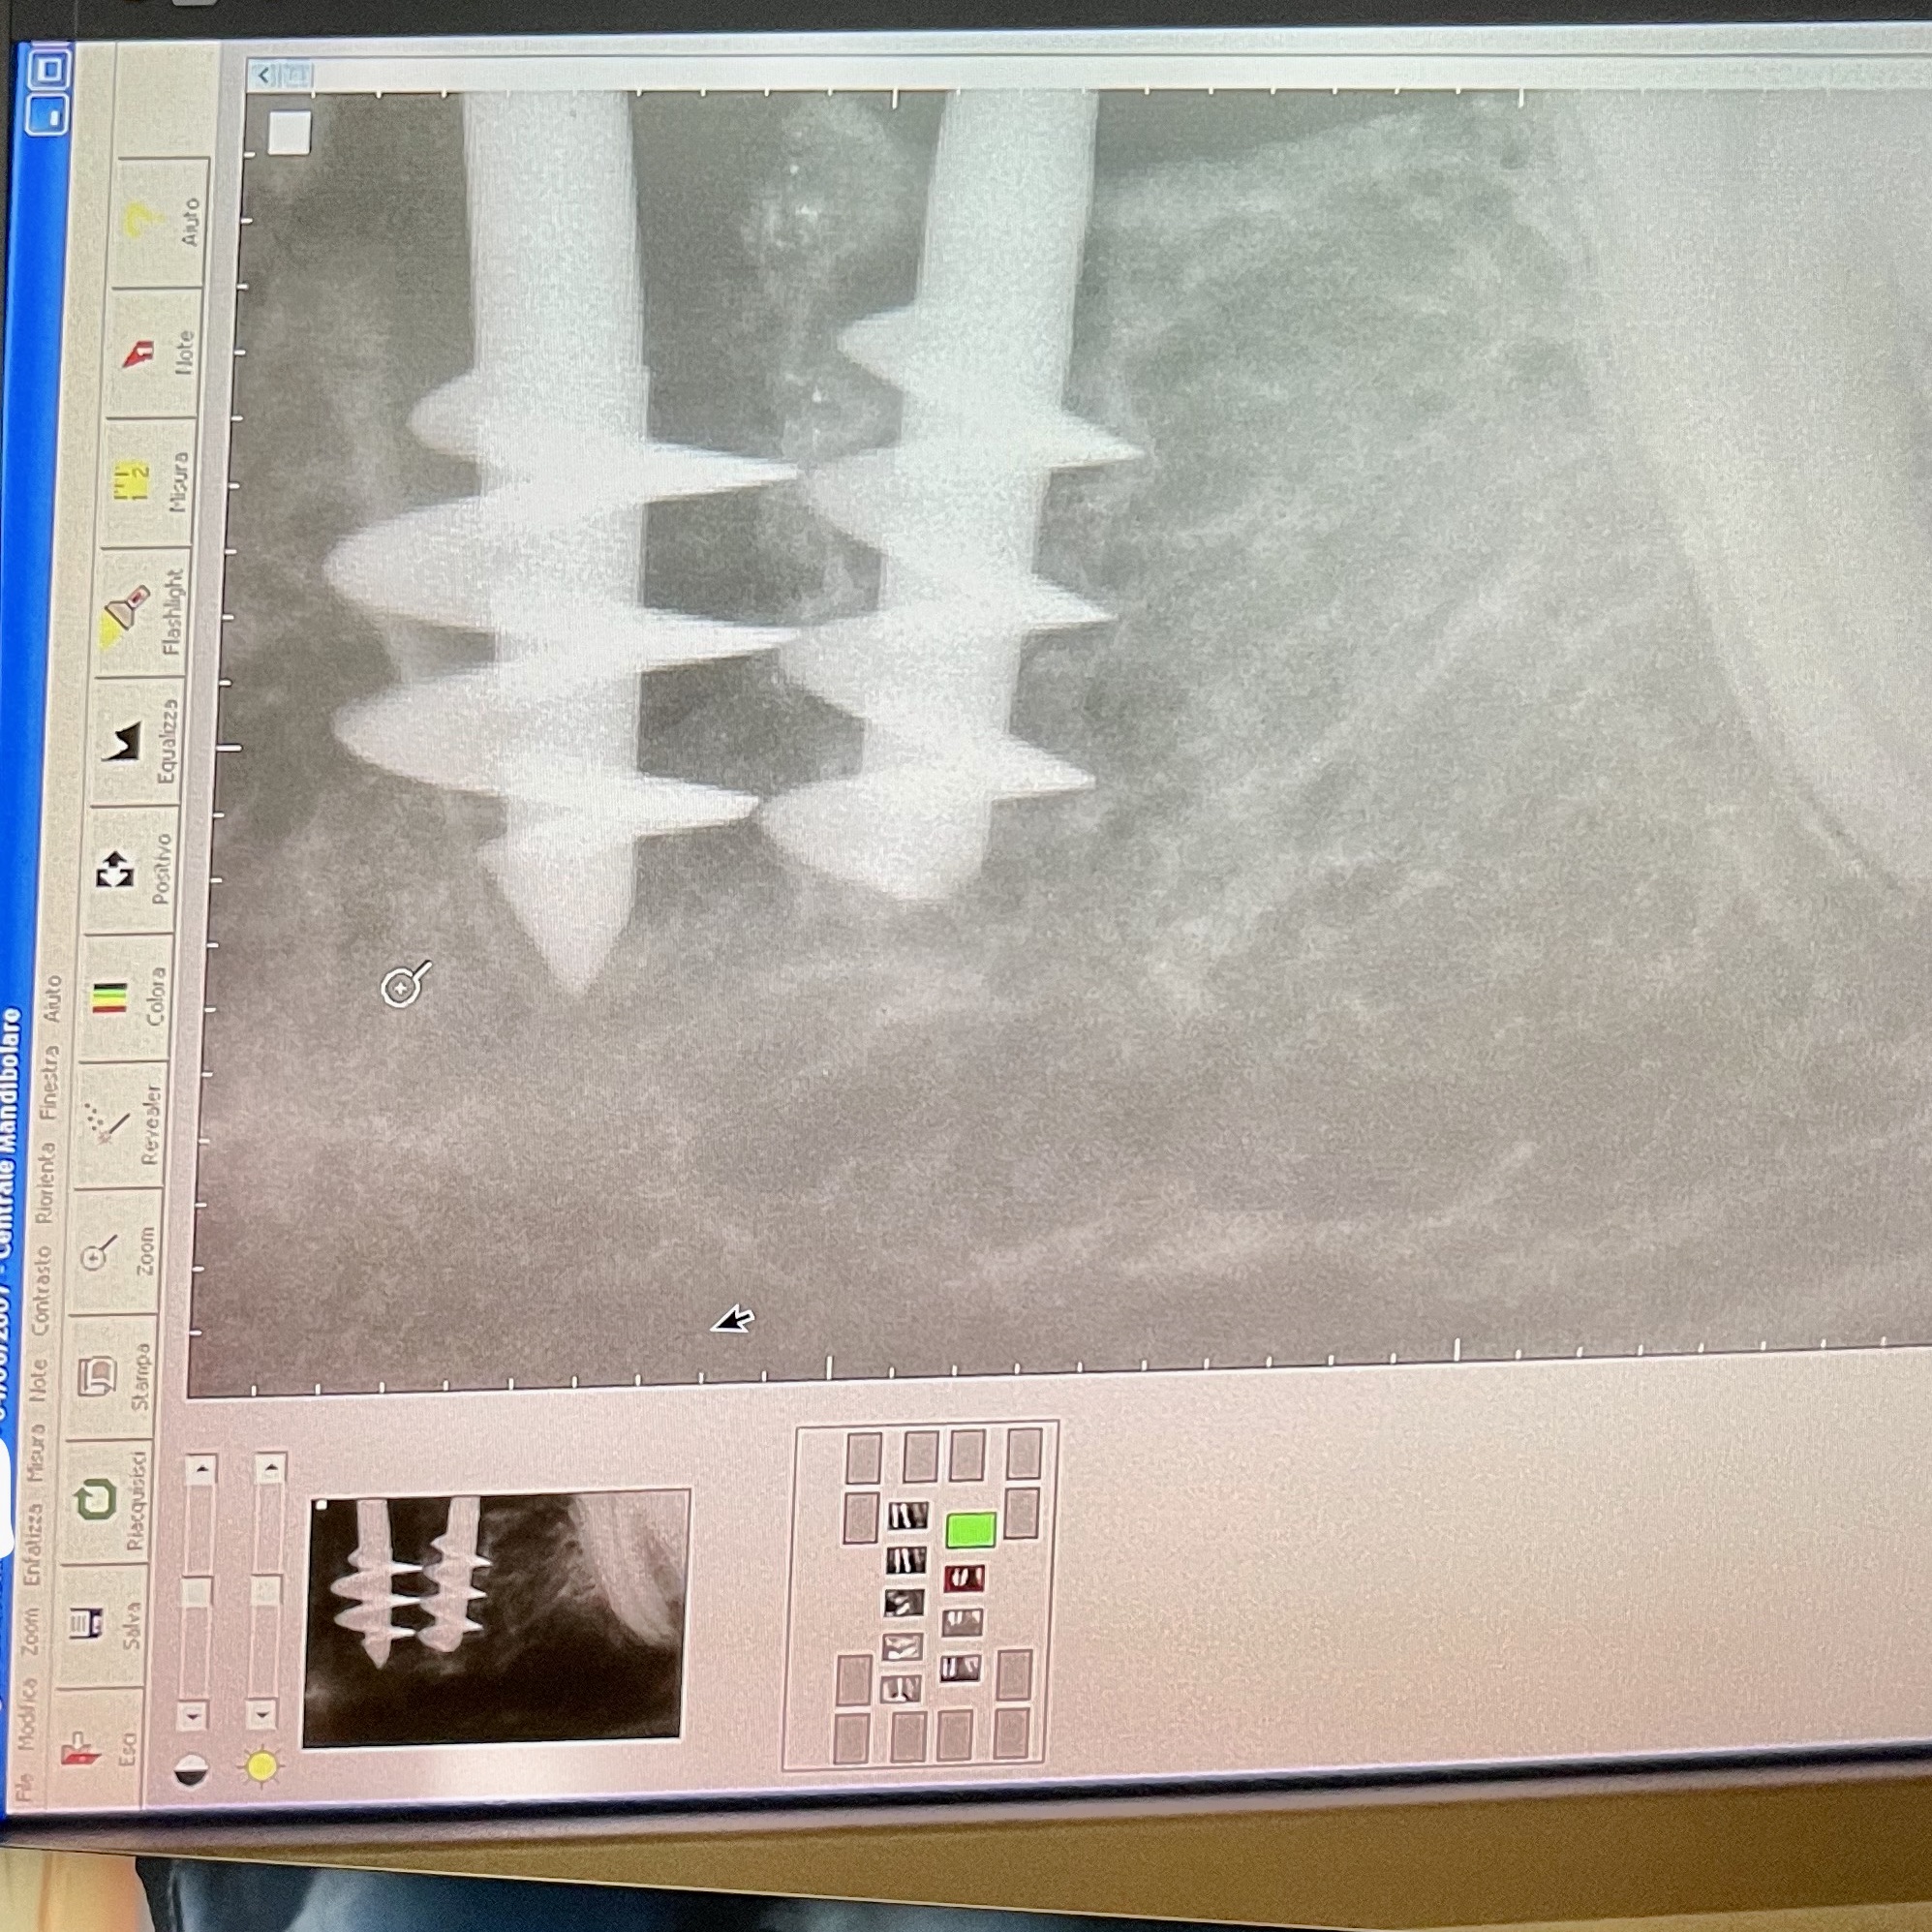

AUTOLOGOUS (with sampling from calvaria or iliac crest or from intraoral sites), HOMOLOGO, (deantigenates of porcine, equine origin), HETEROLOGIST (synthetic bone, hydroxyapatites, calcium sulphate, etc ...). Or... The image exhibited dating back to 20 April 2011 is sufficiently explanatory: there is dense bone around the implants. A graft was certainly made. But no see below rx dated 04 June 2007 which shows two implants of the Italian school inserted in two alveolar cavities, that is two immediate post-extraction implants immediately prosthetic. The new bone formation is all the work of the healing process and the osteoblastic activity resulting from the function.